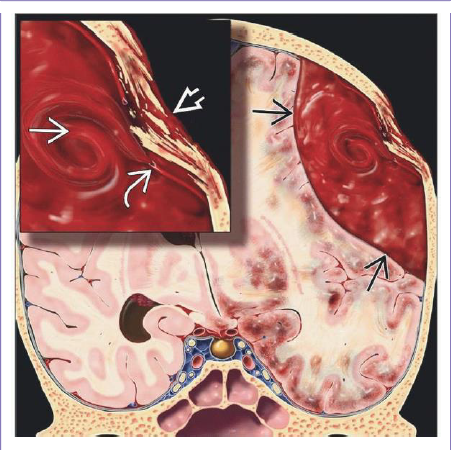

What is your dx?

Graphic depicts crescent-shaped acute SDH with contusions and “contre-coup” injuries , diffuse axonal injuries

What structures have been affected in this pt with SDH?

Acute SDH spreads over left hemisphere , along tentorium , into interhemispheric fissure but does not cross midline.